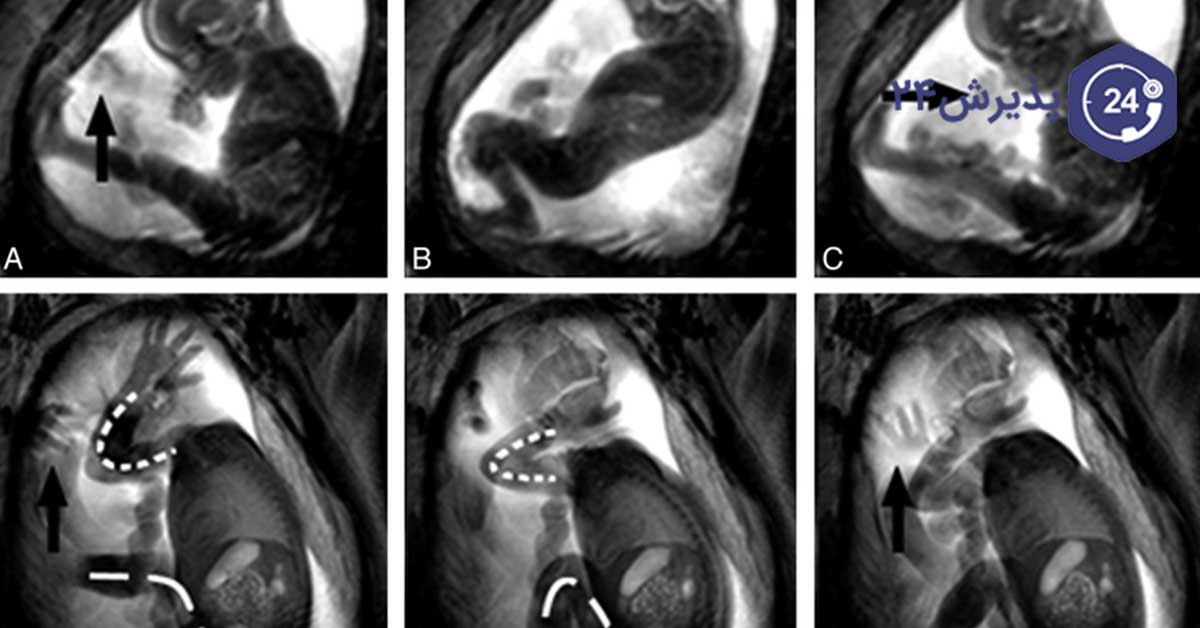

تجربه نشان داده است که تغییرات در حرکت جنین، با افزایش خطر مردهزایی بعد از هفته 28 ام بارداری همراه است. اگرچه پدیده مردهزایی اغلب با توقف یا کاهش حرکت جنین خود را نشان میدهد، اما مطالعات اخیر ثابت کردهاند که ارتباطی بین حرکات بیشازحد جنین و مردهزایی دیرهنگام وجود دارد.

زیرا در مواردی، افزایش ناگهانی حرکات جنین نشانه سازش جنین با اختلالات زمینهای در محیط داخل رحمی است که در صورت تداوم میتواند منجر به مرگ جنین شود. از این اختلالات زمینهای که باعث حرکت زیاد جنین میشوند میتوان به موارد زیر اشاره کرد:

- تشنج جنین ناشی از خفگی یا عفونت

- تلاش جنین برای رهایی از درهمتنیدگی بند ناف

- مواجهه جنین با یک محرک مضر مانند دارو یا سم

- وجود خفگی پریناتال را میتوان با استفاده از امتیاز آپگار، ارزیابی اسیدمی جنین یا اندازهگیری عوامل مرتبط با استرس در خون بند ناف ارزیابی کرد.

- وجود تشنج جنینی یا درهمتنیدگی بند ناف را میتوان با کاردیوتوکوگرافی و سونوگرافی جنین و بند ناف ارزیابی کرد.